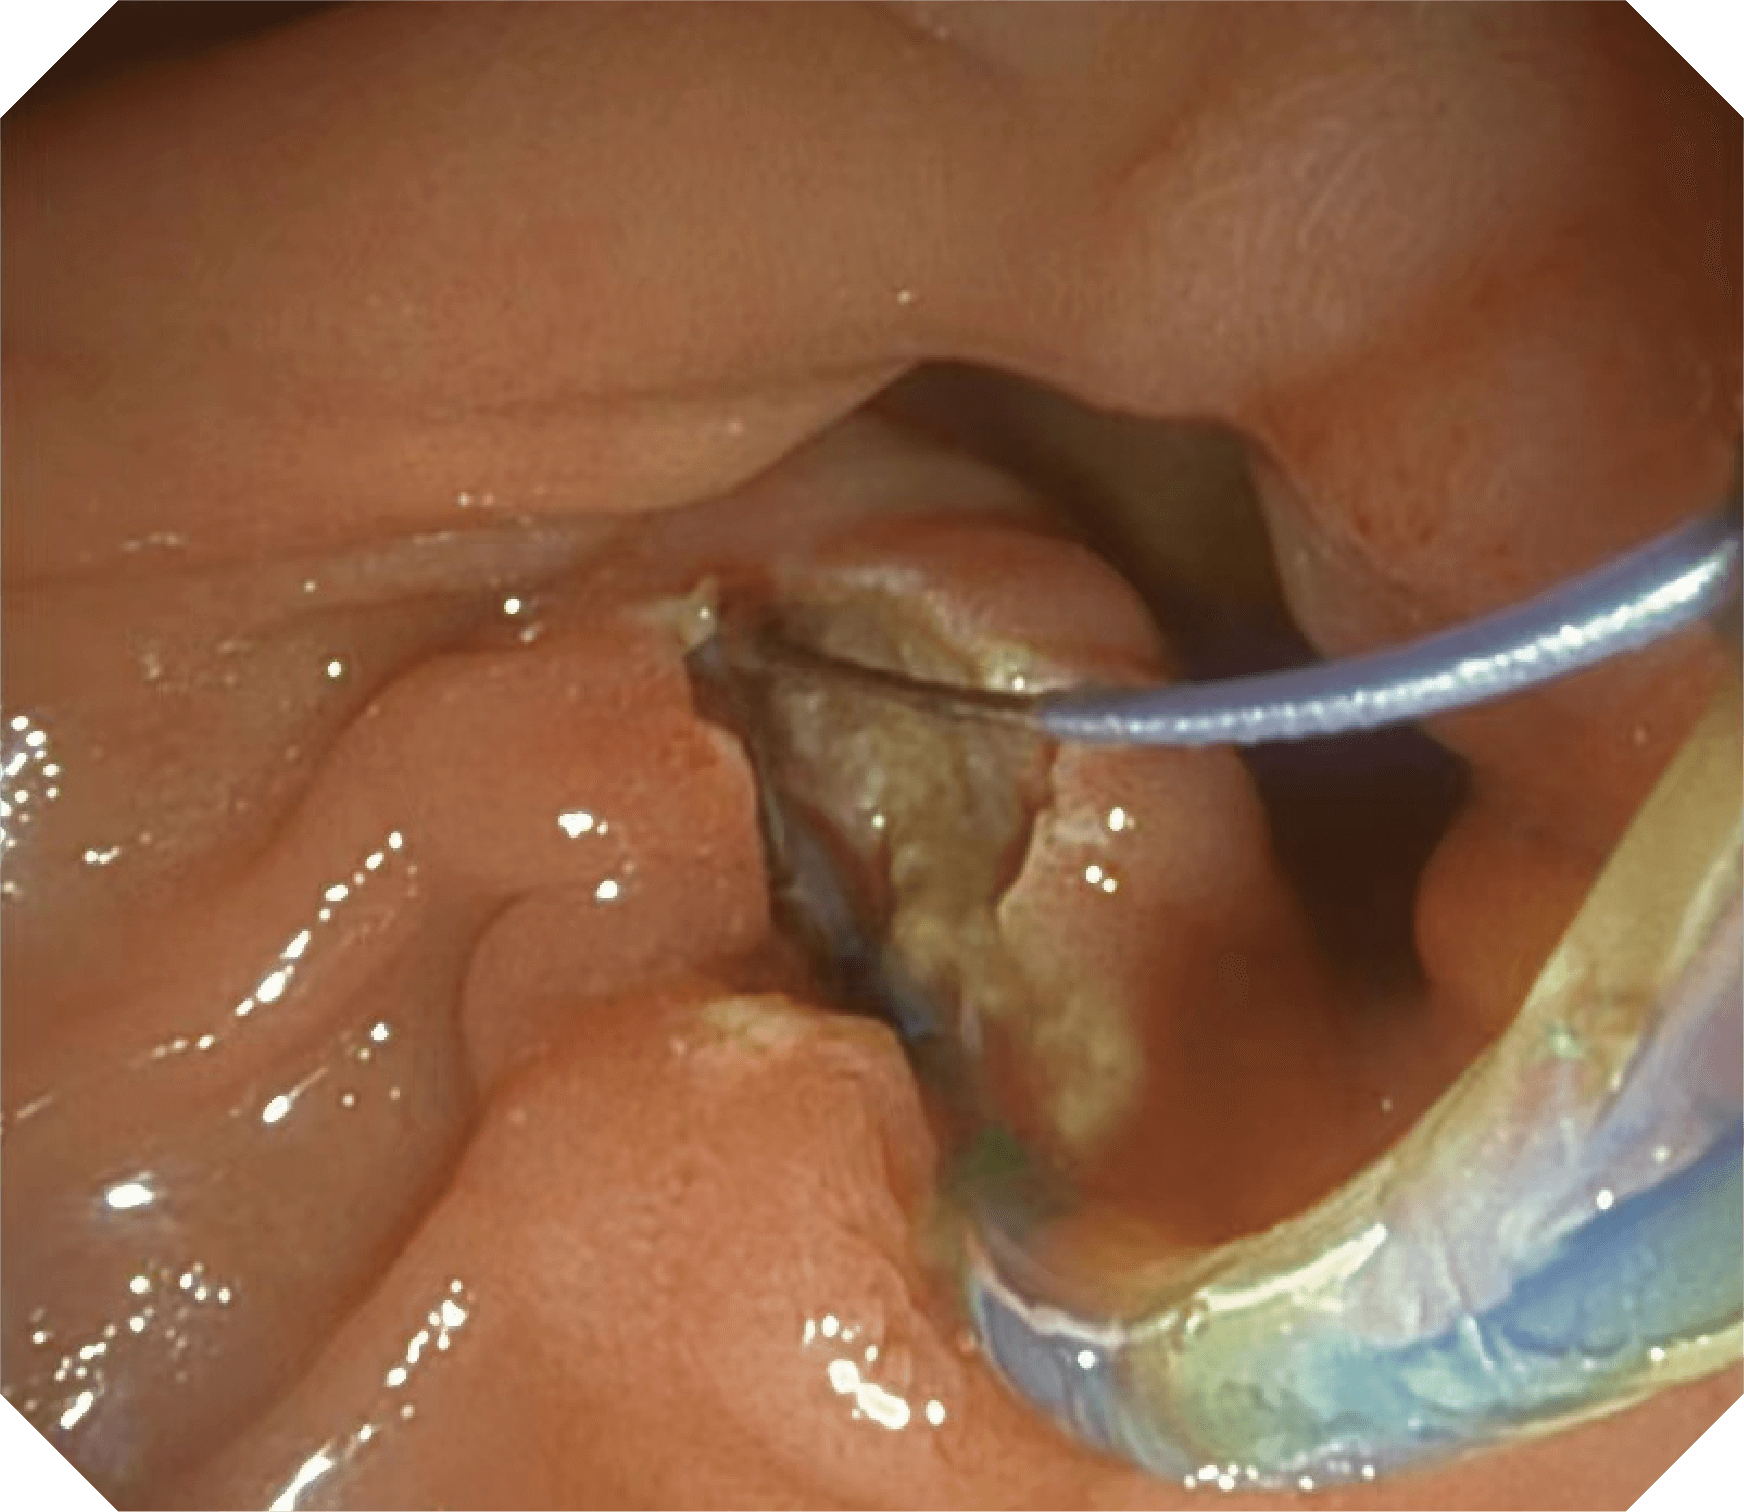

CMOS传感器提供高清内镜视野 SFI/VIST光学染色技术凸显病变区域

4.2mm大钳道,器械交换更顺畅

优异的手术器械抬举性

当切开刀伸出视野外时,导向面引导其回归视野